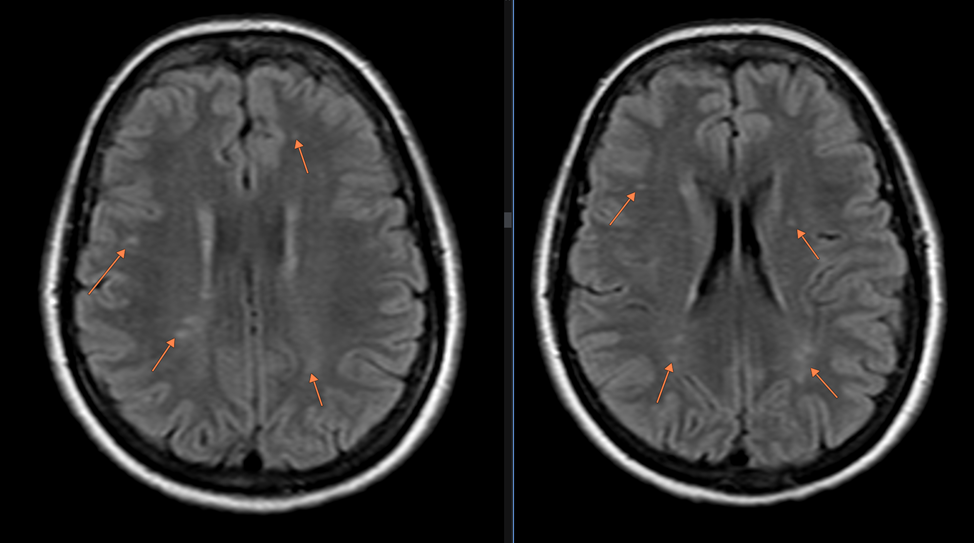

Рис.1: FLAIR аксиальная плоскость. В белом веществе лобных и теменных долей (субкортикально и паравентрикулярно) определяются множественные очаги глиоза (сосудистого генеза), размерами от 0.2х0.2см до 0.65х0.65 см.

Других патологических изменений со стороны головного мозга у пациента не выявлено.